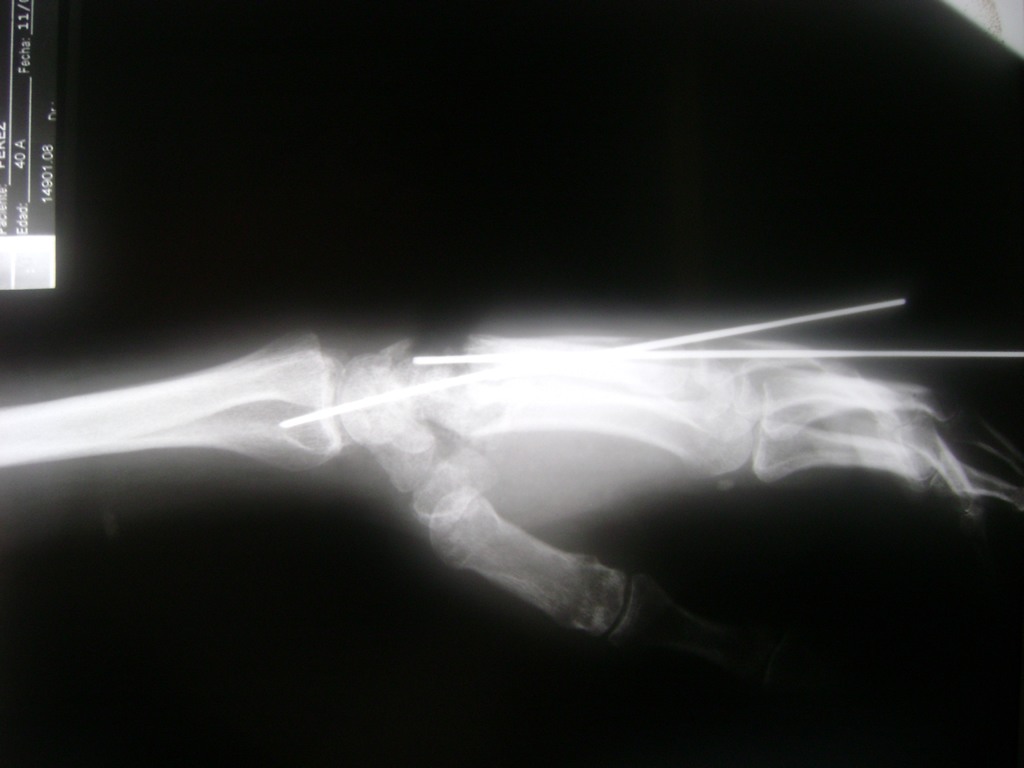

Los procedimientos más comunes en cirugía de la mano son aquellos destinados a reparar traumatismos, incluyendo lesiones de tendones, nervios, vasos sanguíneos, y articulaciones; huesos fracturados; y quemaduras, cortes, y otros daños de la piel.